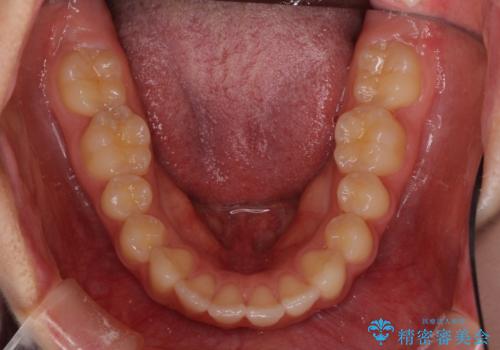

就職前にきれいな歯並びにしたい 大学生のインビザライン矯正

- 就職するまでに歯並びをきれいにしたいとのことで来院された患者様です。

前歯の叢生を気にしていましたが、極力突出感を改善できるようにすることとし、インビザラインにて矯正治療を行うこととしました。

改善の期待できない口元の突出感改善を希望されたため、いたずらに治療期間が延びましたが、きっちりと仕上がりました。